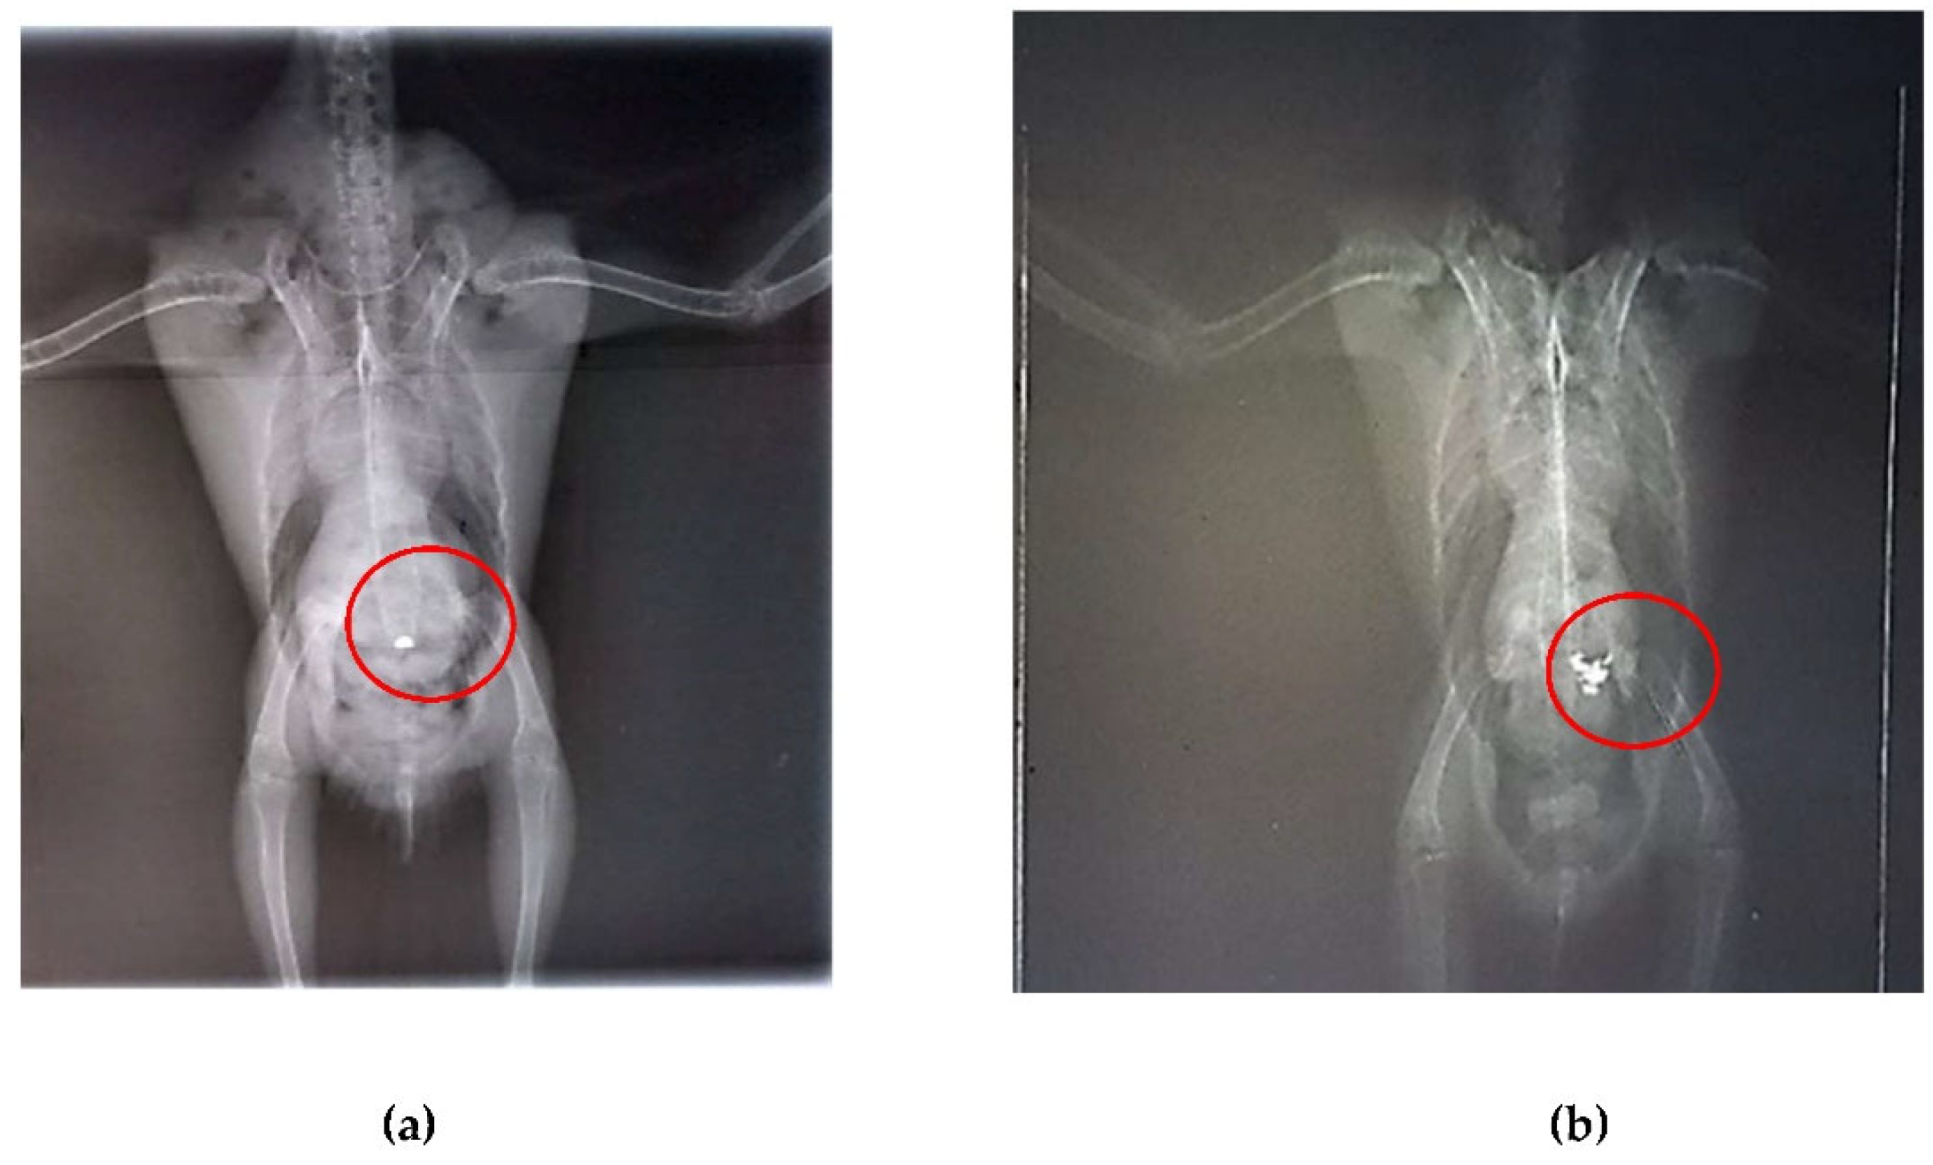

After seven days of chelation therapy, the birds underwent repeat radiographs of the coelomic cavity under sedation with intranasal midazolam (0.01 ml). In these radiographs, a reduction in the amount of metallic content in the ventriculus of bird 1 was observed, and chelation therapy with calcium EDTA was continued for an additional three days. For bird 2, the radiographs taken after the start of chelation therapy showed no remaining foreign bodies in the ventriculus; however, an area of radiopacity was noted in the pulmonary field (Figure 5A, B). It is important to note that no metallic objects were observed in the feces of either bird.

Figure 5. Radiographic examination of the coelomic cavity in two specimens of Aratinga jandaya. (a) Ventrodorsal projection – quantitative reduction of radi opaque content compared to the first examination (marked in red) in the ventricular region the bird 1. (b) Ventrodorsal projection – presence of a few radiopaque foreign bodies (marked in red) in the second bird.